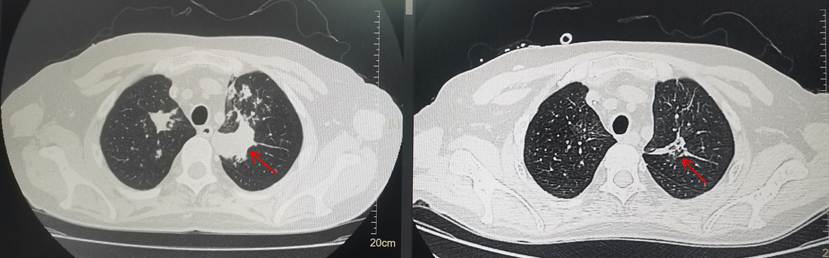

他到医院查胸部CT,显示双肺多发粟粒小结节状、斑片状密度增高影。医生认为张先生是“肺部感染”,先后予以消炎治疗。

但治疗1个月后,张先生的症状没有明显改善。再次复查胸部CT,竟然发现肺部病灶较前增多,病情恶化了。

▲治疗前后 胸部CT对比图

之后,改抗真菌治疗2天,李先生的体温就恢复正常。再次复查胸部CT,显示病灶明显吸收。李先生终于松了一口气。